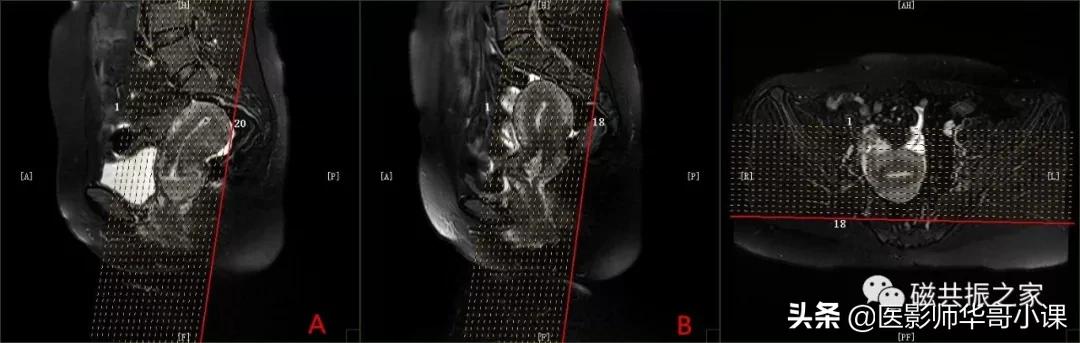

横断面: AX 3D (LAVA、VIBE、THRIVE)(动态),横断面T1加权LAVA多期动态增强扫描序列

在冠状位和矢状位上定位,扫描范围上至子宫上缘下至耻骨联合,需包括整个病变范围,如观察转移性病变需加大扫描范围。第一期蒙片扫描完成后暂停,然后注射造影剂。

在注射药物15S左右开始扫描,连续扫描8~10期。在多期扫描完成后,扫描COR 3D (LAVA、VIBE、THRIVE)及SAG 3D (LAVA、VIBE、THRIVE)序列。

添加上下饱和带,减小血管搏动伪影。

相位编码方向为前后方向。

使用较大的FOV防止卷积伪影(超过解剖的25%),并使用并行采集(加速因子不宜过大)技术可缩短扫描时间。

如扫描时间较长,增加带宽,减少扫描层数,减小相位编码数可缩短扫描时间。

多期扫描完成后作多期扫描动态增强曲线分析。